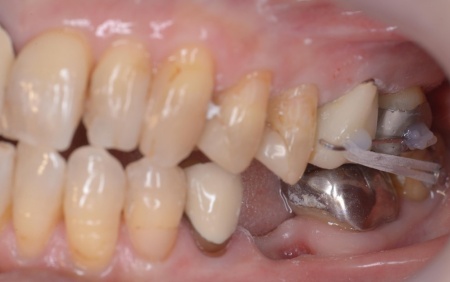

60代女性 割れた奥歯を抜いたあと親知らずを移植して噛み合わせを回復した症例

拝見したところ、左下奥歯(第1大臼歯)が割れていることが判明しました。

割れた歯では噛む力を十分に受け止めることができないため、痛みが生じている状態です。

次に、親知らずの歯根膜をできるだけ傷つけずに抜歯するため、事前に部分矯正(MTM)を行いました。

MTMとは特定の歯のみを動かす矯正治療で、抜歯しやすい状態を整え、移植の成功率を高めます。

歯根膜をなるべく残して抜歯できるよう、親知らずにMTMを行いました。